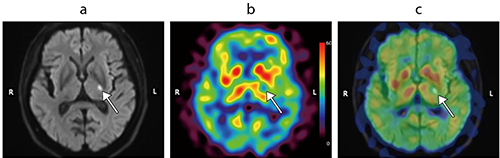

図2 左内包後脚の急性期脳梗塞

a:頭部MRIの拡散強調画像(b=1000)(発症3日後)

b:123I-IMP 190MBqを用いたARG法による脳血流SPECT定量画像(FANHR、Recon:FBP法、TEW法、Iterative Chang法)(発症7日後)

c:Mirada Fusion Standardソフトウェアを用いたSPECT画像と拡散強調画像の融合画像

急性発症の右片麻痺を主訴とする60歳代、男性。拡散強調画像では、左内包後脚に急性期梗塞を反映して高信号域を認める(a ↑)。小病変ではあるものの、SPECT画像において梗塞部位に一致した限局性の血流低下を認めることができる(b ↑)。またMirada Fusion Standardソフトウェアを用いた融合画像を作成することで、左内包後脚の拡散強調画像高信号域と血流低下域とが一致していることを確認できる(c ↑)。